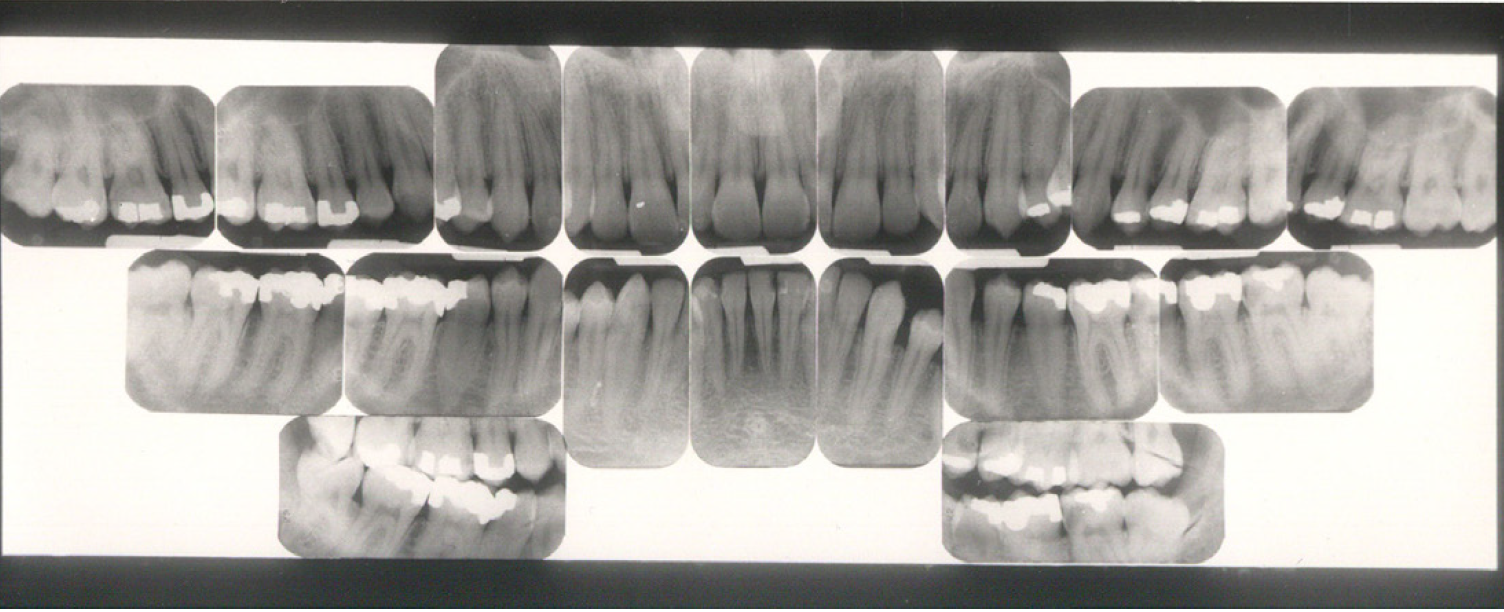

Dentulous Adult Survey

The number of radiographic images needed for a full mouth series varies greatly. Some practitioners may prefer 10 exposures, while others may prefer 18, 20, or more exposures.

The selection of receptor sizes used in a full mouth series also varies. A full survey can consist of narrow anterior (type 1); standard adult (type 2); type 2 bitewing or long bitewing (type 3) (Figure 4) and may include anterior bitewings. It is generally recommended to use twenty radiographic images --- four bitewings and sixteen periapical images. Eight anterior type 1 radiographic images will allow for ease of receptor placement on patients with narrow palates. However, in some cases six anterior periapical images will cover the area needed.

When using type 3 receptors, only one longer bitewing is used on each side. Opening both the premolar and molar contacts on one radiographic image can be very difficult (Figure 5). With the use of type 2 receptors for bitewings, the operator uses a total of four images. Each image is assigned either premolars or molars (Figure 6). Use of the type 2 instead of type 3 radiographic receptors for bitewings is not only more comfortable for the patient but is easier for the operator to open the contacts.